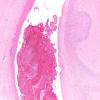

8C2 Infarct, acute (Case 8) N20 H&E 20X